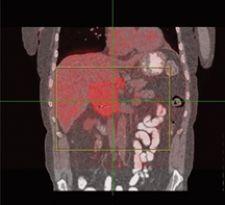

“We’ve taken it one step further with 4-D PET and now have the PET image overlaid with 4-D data to see both anatomy and function,” Dr. Heron explained. “This provides a wealth of data that is absolutely amazing.”

Dr. Heron cites a specific clinical example of 4-D CT/4-D PET imaging’s impact on patient treatment planning. In a patient with an upper abdominal mass, Dr. Heron could not conclusively tell exactly where the tumor was on a typical helical CT scan. He could see the tumor with PET. However, once he fused the images and created a 4-D PET/CT data set, Dr. Heron could identify nearby lymph nodes that weren’t obvious on the helical CT, 4-D CT or PET scans.

“This information dramatically changed our treatment plan for the patient. With the 4-D data, we learned the center of the tumor was hypoxic, and, therefore, we could use that knowledge to deliver more radiation to the center of the tumor,” indicated Dr. Heron.

By using a timed resolution, UPMC can fuse and link together 4-D PET and 4-D CT images to precisely view tumor movement. “It is no longer sufficient to capture only 4-D anatomic images.” Dr. Heron explained, “It’s a natural evolution to also have images depicting 4-D function.”